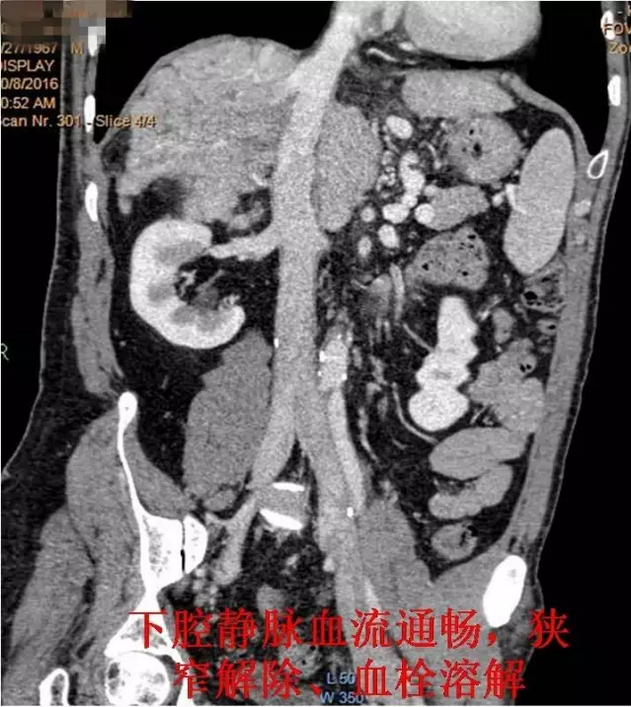

入院后王兵副院长热情接待了郑先生,经过检查怀疑其患上一种罕见的“布加综合征”,经进一步检查,结果证实了判断,明确患者所患疾病为“布加综合征”,而非单纯的“下肢静脉曲张”。同时发现患者合并有下腔静脉(一条通往心脏的大血管)血栓形成。经过科内分析讨论,王兵副院长决定为患者行介入微创治疗。经过详细的术前评估及周密的术前准备,王兵教授带领血管外科崔文军副主任、司江涛主治医师、李攀峰医师为郑先生施行了手术。在局部麻醉下穿刺股静脉后,首先巧妙的在下腔静脉内置入血栓过滤装置,预防血栓脱落导致肺栓塞,然后放置溶栓导管,经导管泵入溶栓药物溶解血栓,待患者血栓溶解后,给予置入球囊扩张导管充分扩张患者下腔静脉重度狭窄处,成功解除下腔静脉狭窄。术后患者下肢皮肤溃疡很快愈合,腹部迂曲扩张的血管消失,手术效果满意。

术后复查CTV